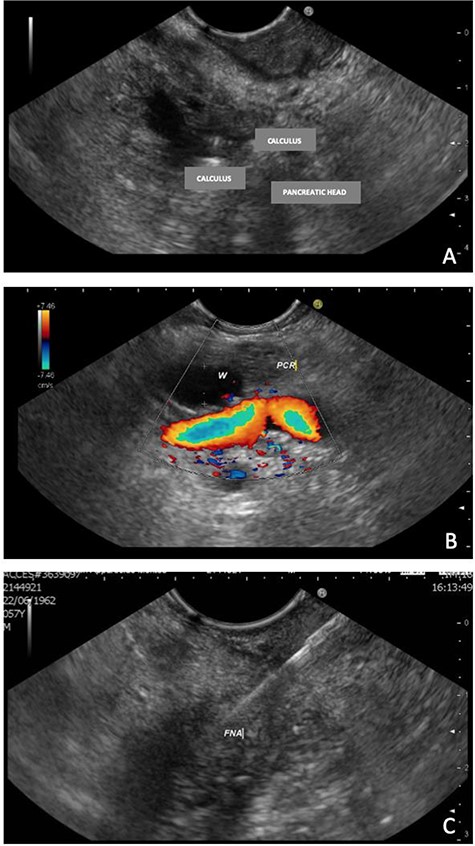

MRI, 1 week after, showed a benign well-circumscribed nodular lesion in the head of the pancreas without contrast enhancement and associated pancreatic stones (Fig. 1).

MRI—hyposignal focus within the main pancreatic duct in the cephalic region, measuring 0.6 cm, associated with irregular dilation of the upstream duct, suggesting stone (arrow).